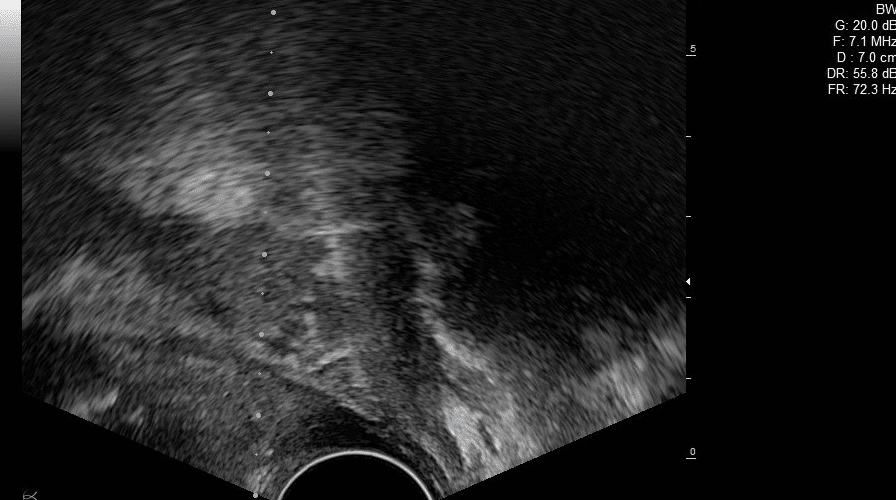

L’ÉCHOGRAPHIE EN UROLOGIE

La place de l’échographie en Urologie ne cesse de croître. Si les services disposent de quelques machines, elles sont souvent réservées à un usage planifié. Or, de plus en plus, la bonne pratique en Urologie nécessiterait de s’assurer de la bonne échogénicité des organes, de l’absence de caillots etc.

L’échographie permet également l’étude précise de la morphologie et de la structure des reins, vessie, de la prostate etc. Et grâce au guide échographie, vous pouvez également réaliser des biopsie de la prostate de manière plus efficace en limitant le risque de complication pour le patient.

Les échographes Sonoscanner, Leader Français de l’Echographie sont équipés d’une sonde linéaire haute fréquence à très haute densité de capteurs. L’image offre une résolution d’une finesse sans pareil et permet de distinguer des structures inférieures au dixième de mm.